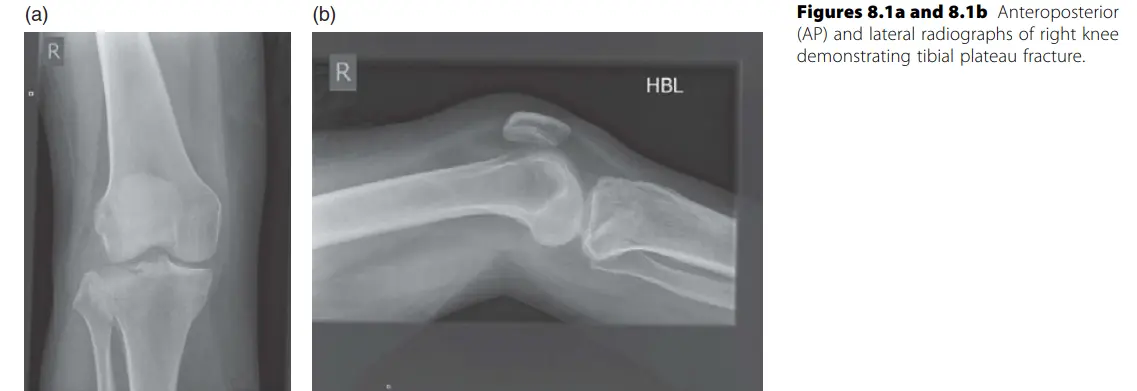

كسور هضبة الظنبوب (Tibial Plateau Fractures): كسور في الجزء العلوي من عظم الساق الذي يشكل مفصل الركبة.

- الأنواع (حسب Schatzker): تتراوح من كسور بسيطة إلى كسور مفتتة.

- المضاعفات: إصابة العصب الشظوي (Peroneal nerve palsy) شائعة، خاصة مع كسور هضبة الظنبوب الجانبية أو النوع الرابع. متلازمة الحيز (Compartment syndrome) هي أخطر مضاعفة مبكرة.

- العلاج: يعتمد على الإزاحة والاستقرار. الكسور المزاحة تتطلب رد وتثبيت جراحي.